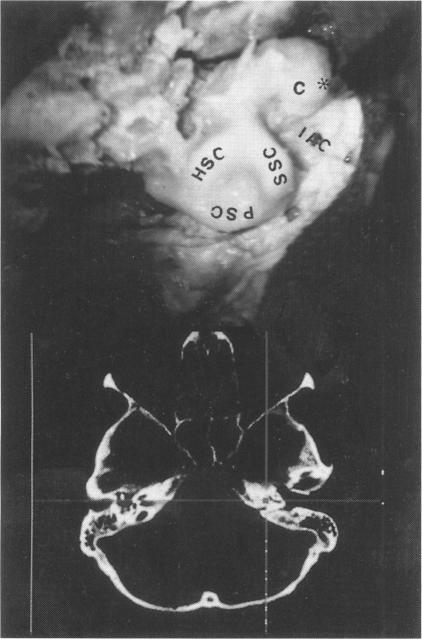

The applicability of an image guidance frameless system based on an opto-electronic sensor device in skull base surgery was explored in this study. Five embalmed heads with external fiducial markers placed in noncoplanar points were scanned (CT scan) and different skull base approaches were reproduced in these specimens. The opto-electronic system is comprised of an infrared camera, a local rigid body, and a 24-light-emitting diode probe attached to different surgical instruments. DOS-based calibration and transformation software and Unix-based surgical planning software were also used. The anatomic landmarks identified during the dissection were matched with the corresponding points derived from computed tomographic (CT) scans. This information allowed the surgeon to develop a three-dimensional representation of the surgical field and to anticipate the next anatomic structure encountered during the dissection. This infrared device operated in real time, is not affected by external factors with regard to its accuracy, and does not interfere with standard neurosurgical techniques. This frameless system is helpful in minimizing the risk of morbidity and provides an accurate guide during the approach, as well as unobstructed access to the surgical field.